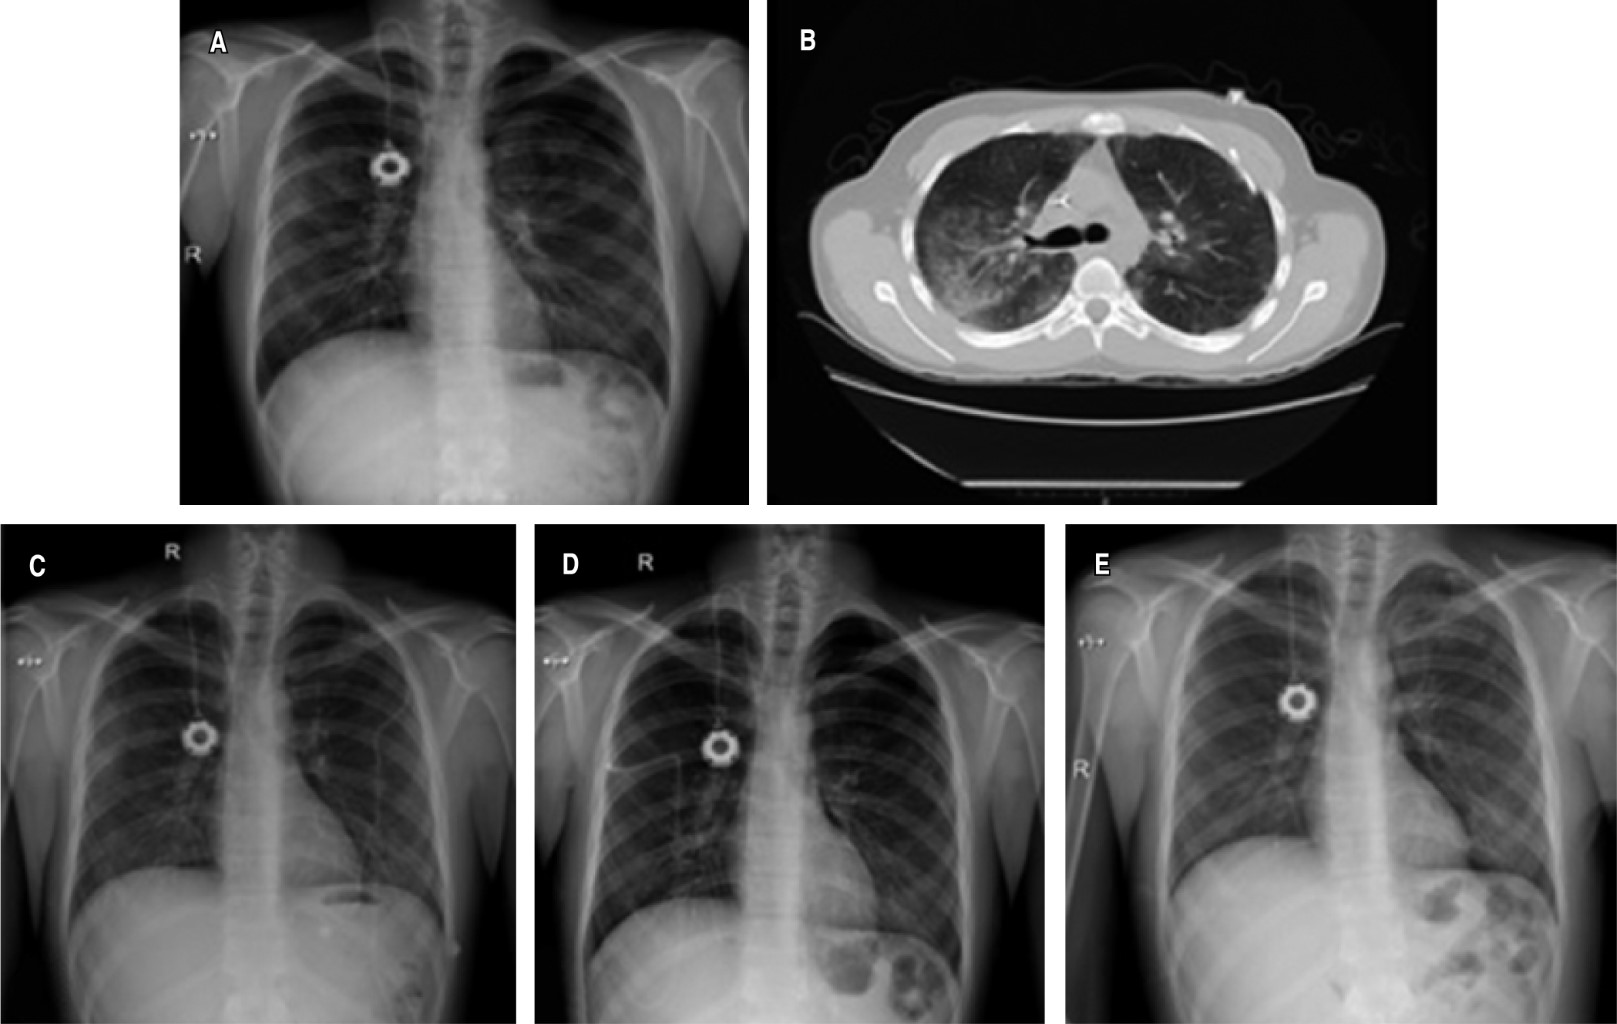

Síndrome de fuga aérea torácica por enfermedad de injerto contra huésped posterior a trasplante alogénico de médula ósea

Montero-Ureña, Raúl Enrique1; Contreras-Rodríguez, Felipe de Jesús2; Márquez-Barajas, Jesús1; Anaya-Gómez, Francisco José1; García-González, Luis Alberto1; Valdez-Rojas, Leonora1; Garnica-Vázquez, Johana Jazer1; Jiménez-Tornero, Jorge1; Díaz-Alba, Alexandra1; Luna-González, Cristina Alejandra1; Álvarez-González, Martha Georgina1; García-Valadez, Yunuen1; Solano-Genesta, Manuel1